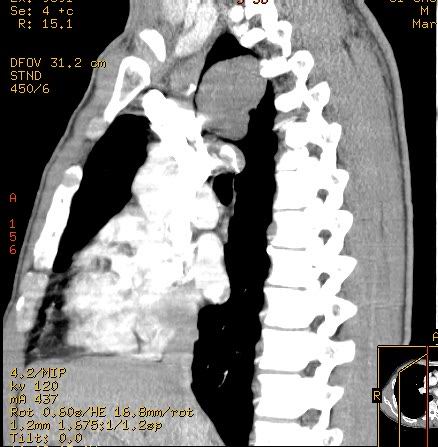

标题: CT7610:[原创]右上纵隔还是肺内占位,请会诊!

体检发现,无任何不适。

不过重建的图片上看到肿块内可见强化的血管影,不是很支持。

右肺见纵隔旁见类圆形界清等密度肿块影,直径约5.0cm,增强呈不均匀强化,重建的图片上看到肿块内可见强化的血管影,考虑:1,肺腺瘤;2,肺肉瘤。

肺内肿块、从轴位像看具备了良性肿块的特点;而重建图像有强化、浅分叶,恶性病变亦不能出外。期待结果。